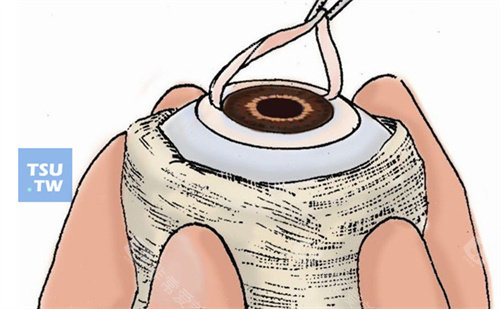

技术亮点:保留健康内皮层,排斥率≤5%,1个月即可拆线

含金量:飞秒激光辅助切口(精度0.1mm),术后散光降低40%

黑科技:3mm微切口植入,无需缝合,术后次日可视物,适合大泡性角膜病变

飞秒激光移植系统实现微米级切割,供体利用率提升40%